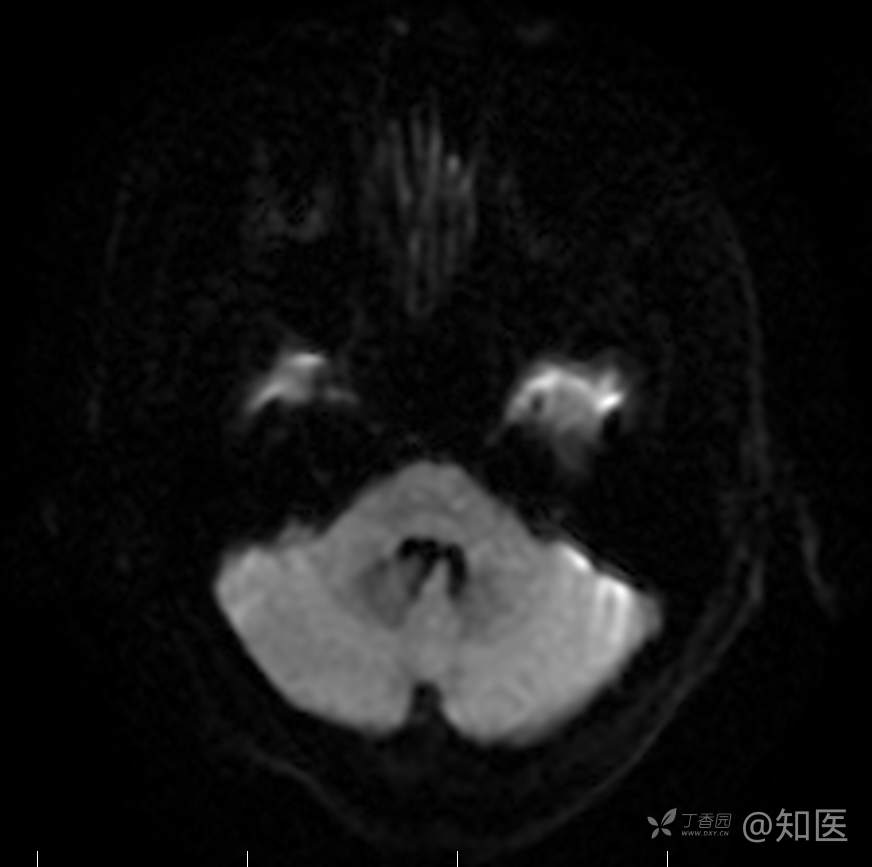

2021-6-15 DWI

2021-06-16日晨查房,患者自觉入院治疗后肢体无力症状较前稍改善,仍有活动后气短,余未诉特殊不适。ALSFRS-R评分:44分(单项均大于等于2分)。血压:123/63mmHg。神经系统查体:GCS 15分,右利手,查体合作,问答切题,粗测智能基本正常。额纹对称,双眼闭目紧,双侧瞳孔等大等圆,直径约3.0mm,对光反射灵敏,眼球运动自如,无眼震,双侧鼻唇沟对称等深,口角无歪斜。悬雍垂居中,双侧软腭抬举良好,咽反射灵敏、转颈、耸肩均一致有力。颈屈肌、颈伸肌力量5级。伸舌居中,无舌肌纤颤及萎缩。双侧岗上肌、岗下肌可见萎缩;双侧三角肌可见偶发肉跳、肌力5级,左侧肱二头肌肌力4+级、右侧4-级,双侧肱三头肌肌力4+级;双手握力可,双手大小鱼际肌及第一骨间肌可见萎缩,左侧明显,左侧手腕背伸力量4级、右侧4+级,双侧拇短展肌肌力4-级,双侧示指伸肌肌力3级,左侧指总伸肌肌力4级、右侧4-级,双侧小指展肌肌力4-级。双上肢肌张力对称减低。左侧肱二头肌反射迟钝、右侧未引出,双侧桡骨膜反射及肱三头肌反射未引出。左侧胸大肌反射阳性、右侧未引出,双侧Rossolimo征阳性、Hoffmann征阴性,下颌反射阴性。腹壁反射未引出。双下肢可见肌肉萎缩,以左侧明显;左侧髂腰肌肌力4级、右侧4-级,双侧股四头肌肌力5级,双足背伸力量3级,左足跖屈力量4级、右足4+级。双下肢肌张力对称基本正常。双侧膝腱反射、跟腱反射迟钝,双侧跖反射消失,双侧巴氏征未引出。右侧大腿外侧肌肉活检瘢痕周围浅感觉缺失,余肢体及躯干深浅感觉正常,共济运动对称正常。颈软,无抵抗,双侧布氏征及克氏征均阴性。辅助检查:微量元素(钙、镁、铁、铜、锌),微量元素测定(铅,镉)[复][2021-6-16 16:11:07]:钙1.19mmol/l;铁9.00mmol/L。急诊电解质七项[复][2021-6-16 10:41:41]:钾3.55mmol/L。血细胞分析+五分类[2021-6-16 9:57:17]:淋巴细胞百分比19.5%。[头颅,扩散成像(DWI)][头颅,磁敏感成像(SWI)][头颅,水抑制成像(FLAIR)][2021-6-16 18:10:50]:1.多发腔梗,脑白质脱髓鞘,脑萎缩。2.DWI:脑实质内未见明显高信号。3.磁敏感成像脑实质内未见明显异常信号灶。MMSE:26分(高中文化水平)。MoCA:23分。ADL评分:14分。ECAS评分:96分(ALS特异67分、ALS非特异29分)。肌电图:提示颈髓、腰髓、胸髓和延髓支配肌肉可见活动期神经源性损害,颈髓和腰髓支配肌肉同时可见慢性期神经源性损害;提示脊髓前角细胞损害可能,请结合临床。心电图大致正常。外送基因检查:TBK1基因杂合子,提示额颞叶痴呆和(或)肌萎缩性侧索硬化症4型。二线主治医师查看患者后示:1.患者基因检查结果显示TBK1基因杂合子,提示额颞叶痴呆和(或)肌萎缩侧索硬化症4型,结合外院影像学检查可见额颞叶萎缩明显,来院后复查头颅FLAIR+DWI+SWI亦提示脑萎缩,量表评估提示认知功能稍减退,ECAS评分基本正常。综上,修正诊断:肌萎缩侧索硬化症(ALS) 额颞叶变性 低钾血症 高血压2级(高危) 多发腔隙性脑梗死。因TBK1基因引起的额颞叶痴呆和(或)肌萎缩侧索硬化症为常染色体显性遗传,患者父亲已逝,母亲健在,诉无明显认知功能障碍或肌肉萎缩等表现,建议患者母亲抽血送检,进一步明确致病基因来源,必要时患者子女也可行基因检查进一步明确。2.患者目前诊断基本明确,根据文献报道,合并FTD的ALS患者整体生存周期较短(约19个月),目前患者发病已1年余,应充分与患者家属沟通病情,告知疾病预后及生存周期情况,同时建议开始口服利鲁唑片,延缓疾病进展。余治疗方案暂不予调整。密观病情变化,遵嘱执行。

2021-06-18出院总结: 卫某某,男,60岁,以“四肢僵硬1年,加重伴无力半年”之主诉入院。查体:生命体征平稳,心肺腹查体无明显异常。神经系统查体:GCS 15分,右利手,查体合作,问答切题,粗测智能基本正常。额纹对称,双眼闭目紧,双侧瞳孔等大等圆,直径约3.0mm,对光反射灵敏,眼球运动自如,无眼震,双侧鼻唇沟对称等深,口角无歪斜。悬雍垂居中,双侧软腭抬举良好,咽反射灵敏、转颈、耸肩均一致有力。颈屈肌、颈伸肌力量5级。伸舌居中,无舌肌纤颤及萎缩。左侧肱二头肌肌力4+级、右侧肱二头肌及双侧三角肌肱三头肌肌力5级;左手大小鱼际肌可见萎缩,左手握2指松、右手握力可,左手拇短展肌、示指伸肌、指总伸肌及抬腕力量3级,右手拇短展肌、示指伸肌、指总伸肌及抬腕力量4-级。双上肢肱二头肌反射、肱三头肌反射、桡骨膜反射均对称减低;双侧Hoffmann征、Rossolimo征、胸大肌反射及掌颏反射阴性,下颌反射阴性。双侧上、中、下腹壁反射可引出。左侧髂腰肌肌力4-级、右侧髂腰肌肌力4级,双侧股四头肌肌力5-级;右足背伸力量3级、左足背伸力量2级,双足跖屈力量5级。双下肢膝腱反射、跟腱反射对称减低;双侧膝阵挛、踝阵挛未引出。双侧巴氏征、Chaddock征均未引出。右侧大腿外侧肌肉活检处周围浅感觉减退,余四肢及躯干部深浅感觉正常,共济运动对称正常。颈软,无抵抗,双侧布氏征及克氏征均阴性。辅助检查:肌电图(2021-05-08,某军医大学附属医院):神经源性损害(颈段、腰骶段受累,胸段可疑;重复神经电刺激(低频、高频)可见左腋神经递减现象。 肌肉活检(2021-05-18,某军医大学附属医院):(右股四头肌)考虑神经源性损害,建议结合临床除外运动神经元病等。入院诊断:1.肢体无力:肌萎缩侧索硬化症(ALS);2.高血压1级(中危)。入院后查血清蛋白电泳:α2-球蛋白6.50%。凝血六项:血浆凝血酶原时间比值0.93;凝血酶原国际标准化比值0.93。贫血因子三项:维生素B12>1476.00pmol/L。平诊肝功十三项+平诊心肌酶谱五项+血同型半胱氨酸测定+平诊血脂八项+平诊肾功七项+平诊电解质八项:尿素3.05mmol/L;肌酐49umol/L;钾3.15mmol/L;高密度脂蛋白0.99mmol/L;载脂蛋白A1.131g/L;脂蛋白(a)333mg/L;肌酸激酶420U/L;总胆红素22.1umol/L;直接胆红素5.4umol/L。微量元素(钙、镁、铁、铜、锌),微量元素测定(铅,镉):钙1.19mmol/l;铁9.00mmol/L。急诊电解质七项:钾3.55mmol/L。血细胞分析+五分类:淋巴细胞百分比19.5%。[头颅,扩散成像(DWI)][头颅,磁敏感成像(SWI)][头颅,水抑制成像(FLAIR)]:1.多发腔梗,脑白质脱髓鞘,脑萎缩。2.DWI:脑实质内未见明显高信号。3.磁敏感成像脑实质内未见明显异常信号灶。MMSE:26分(高中文化水平)。MoCA:23分。ADL评分:14分。肌电图:提示颈髓、腰髓、胸髓和延髓支配肌肉可见活动期神经源性损害,颈髓和腰髓支配肌肉同时可见慢性期神经源性损害;提示脊髓前角细胞损害可能。血尿粪常规、免疫八项、风湿三项、血沉、传染指标、血同型半胱氨酸、糖化血红蛋白等未见明显异常。心电图、肺通气功能大致正常。住院期间给予营养神经、清除氧自由基等对症支持治疗。现患者诊断基本明确,生命体征平稳,一般情况良好,可予今日出院。出院诊断:1.肌萎缩侧索硬化症(ALS);2.额颞叶变性;3.低钾血症;4.高血压2级(高危);5.多发腔隙性脑梗死。出院医嘱:1.注意休息,加强营养,低盐、高蛋白高纤维素饮食,注意休息,适当锻炼,避免剧烈运动及重体力劳动。2.出院继续口服药物:甲钴胺 500ug/次,3次/日;辅酶Q10 10mg/次,3次/日;维生素E 100mg/次,2次/日;美金刚 10mg/次,1次/日;利鲁唑片,50mg/次,2次/日,与餐间隔1.5-2小时。3.出院继续用依达拉奉(必存)60mg+0.9%氯化钠 200ml,静滴,1次/日(首疗程14天,后每疗程10天,间隔20天,共使用6个疗程)。4.1月后门诊复查血常规、肝肾功能、电解质功能;3月后我科门诊再次复诊。5.不适随诊。